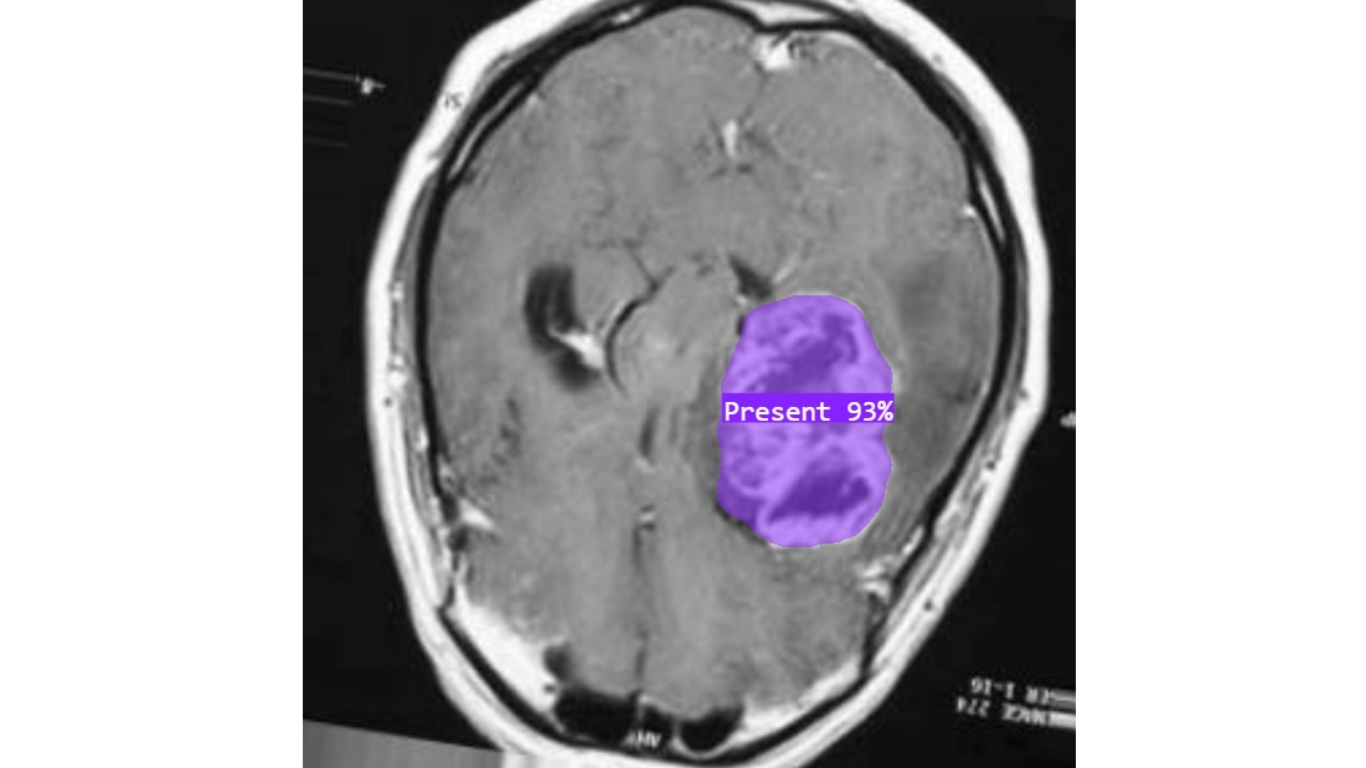

Vertex AI hỗ trợ huấn luyện các mô hình phân đoạn hình ảnh, giúp phân tích chi tiết hình dạng, ranh giới và các vùng quan trọng trong ảnh. Một số ví dụ ứng dụng:

- Khoanh vùng khối u trên ảnh MRI trong lĩnh vực chăm sóc sức khỏe.